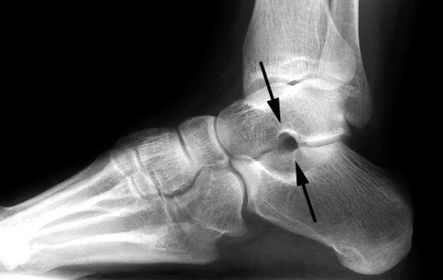

What disease is this? What does the arrow indicate? | Rheumatoid arthritis. Arrow = Bone erosion secondary to inflammation of retrocalcaneal bursa. |

What disease is this? What do the arrows indicate? | Gout Arrows = 'punched out' erosions |